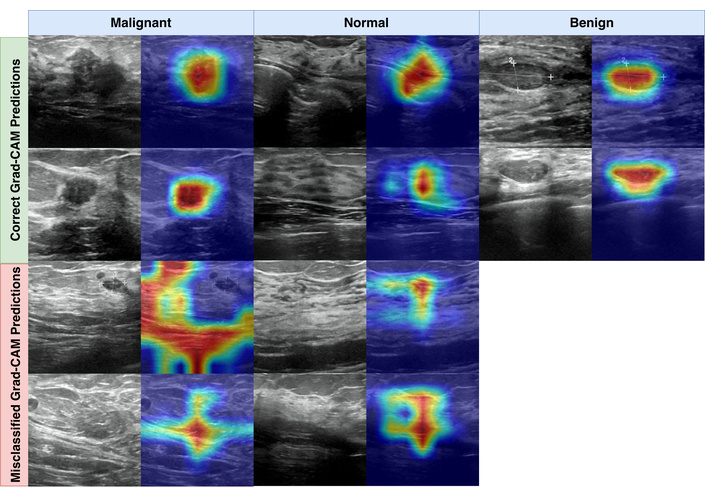

Grad-CAM examples for Swin Transformer Base, showing representative correct and misclassified predictions.

To complement the quantitative metrics, we inspected model behavior using Grad-CAM. Grad-CAM produces heatmaps that indicate which regions contributed most strongly to the predicted class. Heatmaps were generated using the PyTorch Grad-CAM library. For transformer models, maps were extracted from the final normalization layer of the last transformer block, and for CNN models from the final convolutional layer. Saliency maps were normalized with min-max scaling to support consistent visual comparison.

Figure 3 shows representative examples of correct and incorrect predictions. In correctly classified malignant and benign cases, the heatmaps frequently concentrate around lesion regions and their immediate boundaries. For correct normal predictions, attention tends to be distributed across broader tissue patterns rather than focusing on a single focal structure. In misclassified examples, heatmaps can become diffuse or shift toward dense parenchymal regions, which is consistent with common ultrasound challenges such as speckle, low contrast boundaries, and tissue patterns that visually resemble benign margins. These visualizations are post hoc and should be interpreted as supportive qualitative evidence rather than definitive localization of pathology.

Figure 4 provides additional examples with associated prediction confidence values. In the true prediction panel, correct predictions across classes often exceeded confidence 0.9300. In the misclassified panel, errors aligned with the main confusion matrix patterns, including malignant and normal cases predicted as benign, with example confidence values of 0.5060 and 0.5080. These borderline confidence levels suggest that at least a subset of errors may occur in visually ambiguous cases where the model does not strongly separate competing classes.